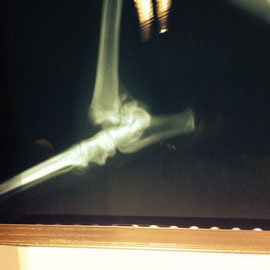

Manchita est arrivée au refuge le 6 mars dernier. Sa patte arrière droite est en mauvais état, elle ne l'appuie pas sur le sol. Cette patte n'a pas beaucoup de masse musculaire. D’après les radios, il semblerait qu'elle ait la cheville cassée, mais elle ne semble pas en souffrir pour le moment.

- Le cas de MANCHITA est beaucoup plus grave et délicat. Elle souffre d’une fracture du tarse et de la cheville, avec les os décalés. La fracture est ancienne. L’opération est « lourde », il faut placer une plaque de chaque côté, angulée et faite sur mesure. Et suivant la fracture il est parfois impossible de mettre des plaques… il faut alors couper l'os. La belle aura donc une patte légèrement plus courte, elle aura une boiterie mais plus aucune douleur ni gêne pour courir et vivre normalement ! Le coût de l’opération de fixation de l’articulation est de l’ordre de 700€.